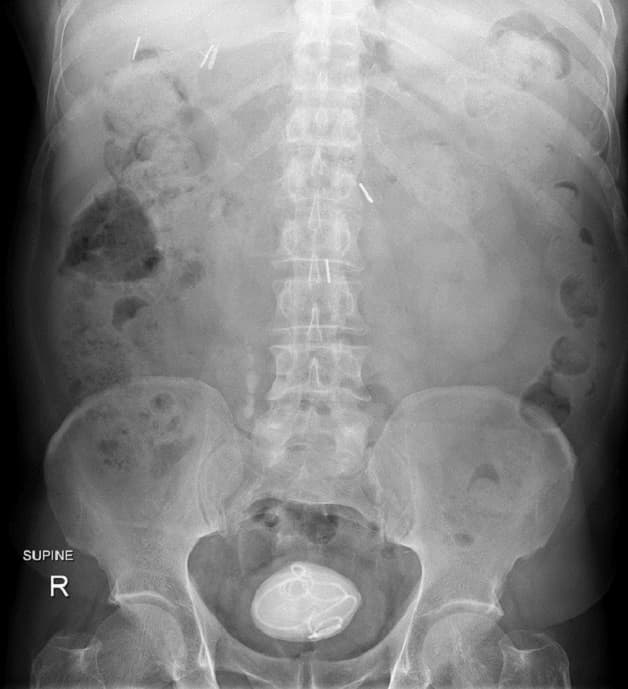

4.3 Chụp X-Quang vùng hạ vị

Chụp X- quang là phương pháp giúp chẩn đoán chính xác nhất sỏi đã rơi xuống bàng quang hay chưa. Hình ảnh thu được còn giúp xác định kích cỡ và vị trí của sỏi

Chụp X – quang giúp đánh giá được tình trạng sỏi